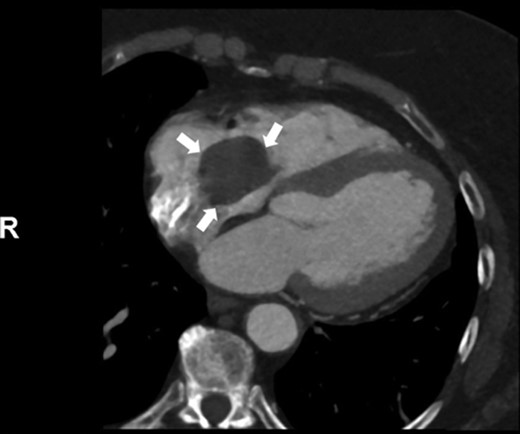

CT cardiac angiogram showed a large filling defect within the right atrium and dense calcification within the aortic valve leaflets (Fig. 2).